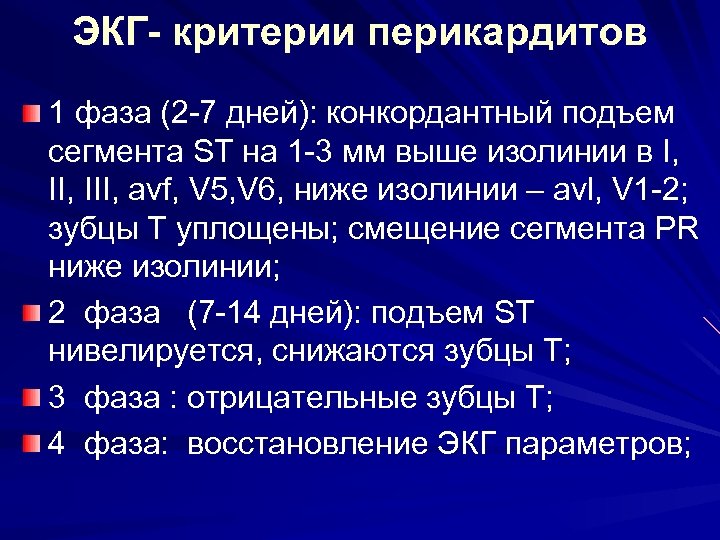

ЭКГ- критерии перикардитов 1 фаза (2 -7 дней): конкордантный подъем сегмента ST на 1 -3 мм выше изолинии в I, III, avf, V 5, V 6, ниже изолинии – avl, V 1 -2; зубцы Т уплощены; смещение сегмента PR ниже изолинии; 2 фаза (7 -14 дней): подъем ST нивелируется, снижаются зубцы Т; 3 фаза : отрицательные зубцы Т; 4 фаза: восстановление ЭКГ параметров;